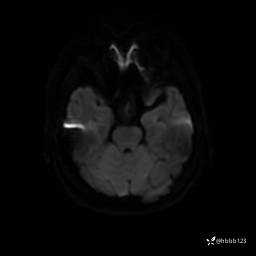

DWI:

ADC: